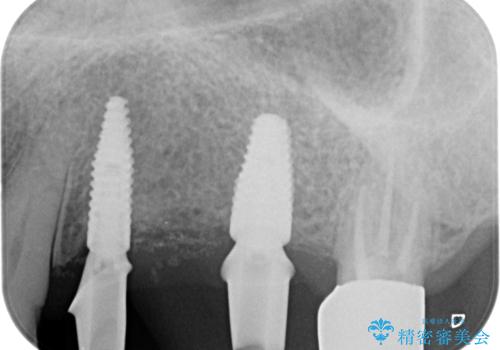

- 奥歯を失い半年間入れ歯を使用してみたが、とにかく咬めない、食事を楽しむことができない!と

咬合機能の回復を求めて来院されました。

しっかりとまた物を噛めるようになるために、インプラントを用いて咬合機能を回復していきます。

- 106.7万円(インプラント×2・チタンカスタムアバットメント×2・ジルコニアクラウン×3・仮歯×3)費用は治療当時の料金となります